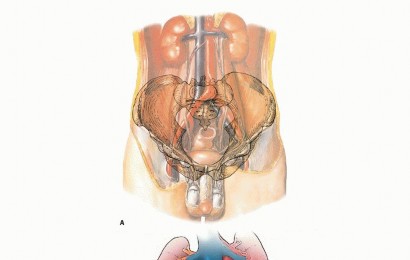

Total Hip Arthroplasty (THA): Comprehensive Guide to Epidemiology, Anatomy, and Biomechanics

- Total Hip Arthroplasty Dislocation: Comprehensive Guide to Causes, Prevention, and Management